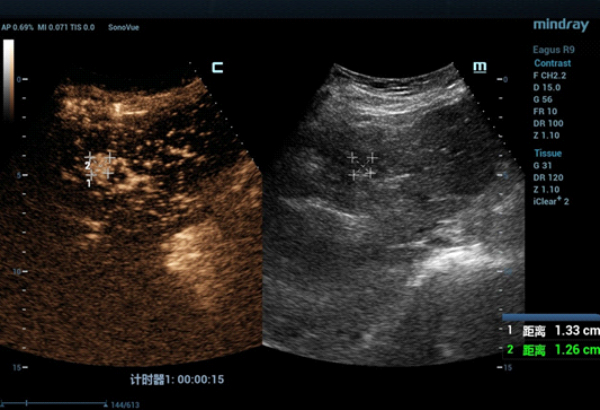

The S4 tumor seen on abdominal CT could not be demonstrated on conventional gray-scale ultrasound imaging. On contrast-enhanced ultrasound (CEUS) the lesion demonstrated hypervascularity in the arterial phase (Fig. 2) with iso-enhancement in the portal and late phases (Fig. 3).